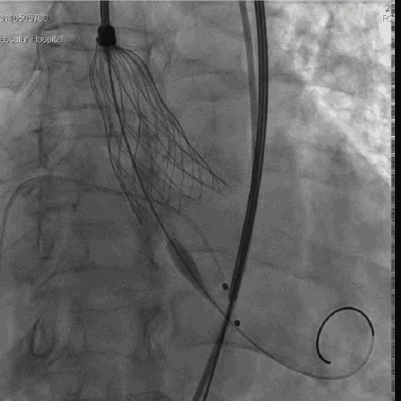

右窦中心位 标准位释放瓣膜

人工瓣膜位置、形态良好,无反流

术中,先对人工瓣膜进行定位,到达预期位置后精准释放,手术结果令人满意。

“慢-快-慢”步骤释放瓣膜,20mm球囊后扩 瓣膜形态进一步优化

球囊后扩后瓣膜形态良好